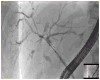

Fig. 1. Typical cholangiographic findings of primary sclerosing cholangitis

Endoscopic retrograde cholangiography showing the typical cholangiographic findings of primary sclerosing cholangitis with multifocal stricturing and dilatation of the bile ducts.